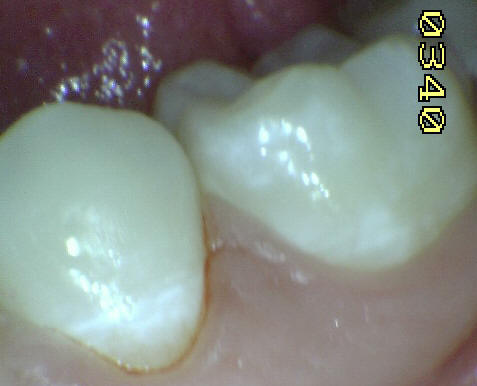

Esmalte liso, traslucido y

cristalino, con finas bandas horizontales de color

blanquecino. |